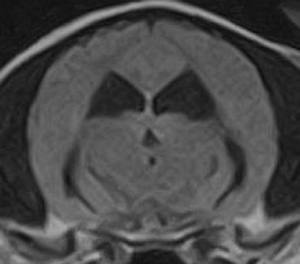

けいれん発作が出るワンちゃんが来院されました。MRI検査では脳に構造上の異常を認めず、特発性てんかんとの診断でお薬での治療となりました。発作は現在のところ、お薬で良好にコントロールされています。